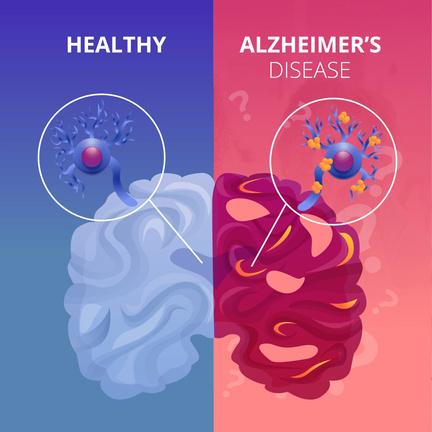

Alzheimer’s disease is one of the most common forms of dementia, a progressive brain disorder that slowly, and gradually destroys memory, thinking skills and the ability to carry out mundane tasks. It is caused by an abnormal build up of amyloid (an abnormal, misfolded protein which accumulates in the tissues and organs) and tau proteins (a crucial neuronal protein, that is the internal scaffolding of neurons that helps maintain their cell shape and transport nutrients and other essential molecules) in the brain which form plaques and tangles that damage the brain cells.

Some symptoms that may present are, memory loss, problems with thinking and reasoning, difficulties with language, planning and organisation, and changes in mood and behaviour. The exact cause is yet to be discovered/understood, however the gut microbiome is linked to its development.

Image from alzheimersla.org